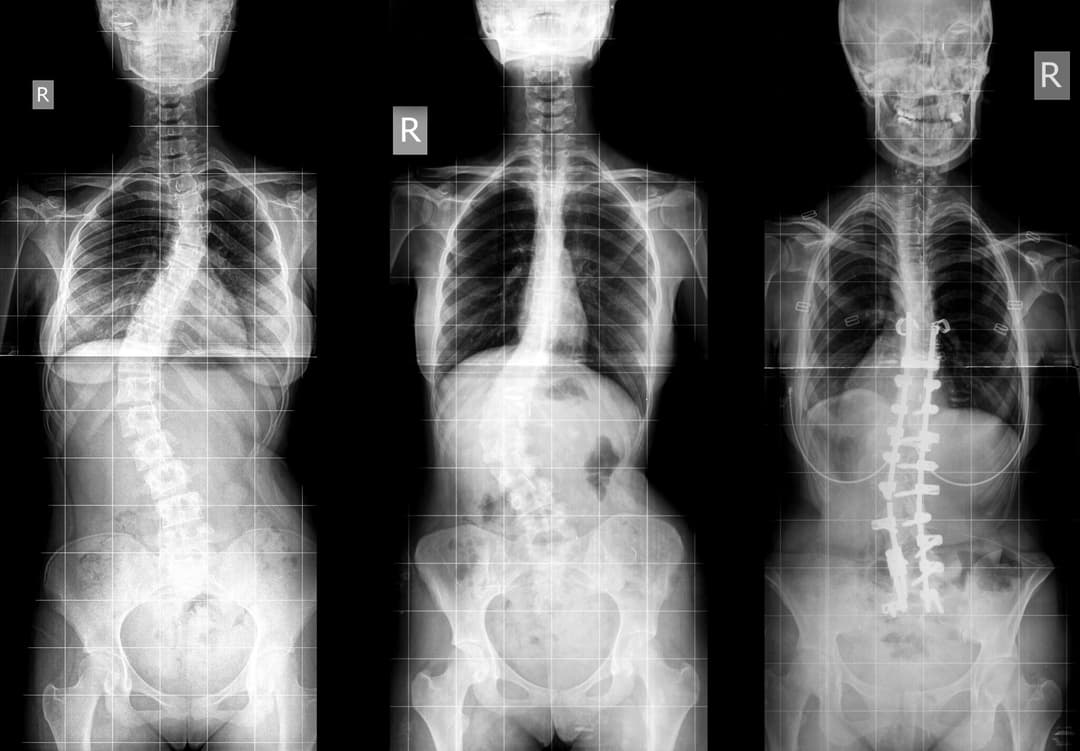

Adolescent idiopathic scoliosis (AIS) is a fairly common spinal condition that affects children between the ages of 10 and 18.

The spine, instead of growing in a straight line, develops a sideways curve, often in an "S" or "C" shape with slight rotation. This abnormal curve can increase in size during growth spurts.